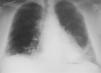

Observación clínicaPaciente de 34 años, que fue derivado a nuestras consultas para el estudio de una disnea de esfuerzo progresiva, con radiografía de tórax que mostraba un patrón intersticial reticular y bibasal (fig. 1). Trabajaba de albañil, era exfumador de 40 cigarrillos/día desde hacía 8 meses (30 paquetes-año) y entre sus antecedentes personales destacaban psoriasis, artritis psoriásica, rinoconjuntivitis y asma alérgica extrínseca con prueba de punción positiva para polen de gramíneas, por lo que había realizado inmunoterapia durante varios años (había finalizado el tratamiento 12 años antes), meningitis sin diagnóstico microbiológico y sin secuelas que había requerido ingreso en la unidad de cuidados intensivos. La clínica consistía en tos seca y disnea a grandes esfuerzos de un año de evolución (grado 1 de la escala del Medical Research Council), que había pasado a ser de grado 2 en los últimos 8 meses y de grado 3 en el último mes. En el momento de la consulta recibía tratamiento con indometacina de liberación lenta (un comprimido al día) y deflazacort (15mg/ día), prescritos por el Servicio de Reumatología. Había recibido tratamiento durante más de un año con metotrexato, que había abandonado hacía 2 por iniciativa propia, y con etanercept en el último año, hasta 15 días antes de acudir a nuestra consulta.